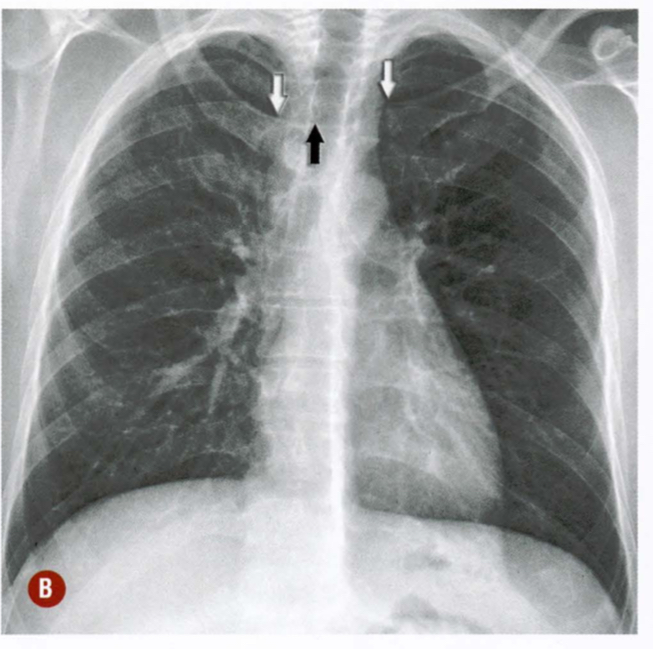

Qual a alteração demonstrada pelas setas?